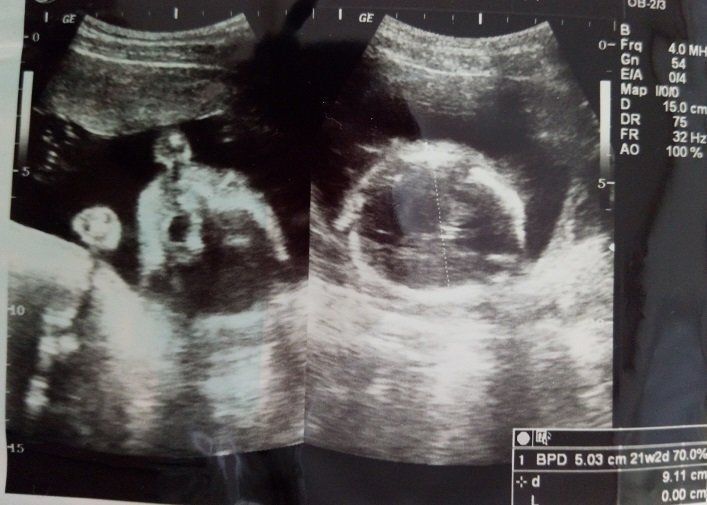

妊娠26週のエコー写真 4Dエコーに感動

初めて4Dのエコーで検査をしました。この日に性別を教えてもらえることになっていたので、とても楽しみに臨んだ検査では、股をしっかり開いて「男の子」を主張してくれました。右側に映るのが赤ちゃんの横顔です。顔がはっきりと見え、嬉しくて何度も見返していました。でも鼻が低いのが私に似ているようで、「可哀そうに」とも思っていました。